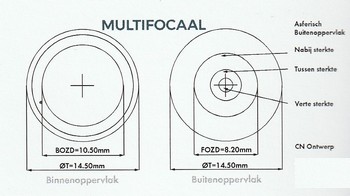

Met een enorme precisie wordt een leesdeel in de lens van bijvoorbeeld 10 mm doorsnee geslepen.

Een multifocale lens zit vrijwel onbeweeglijk in het oog, bij een multifocale lens kijkt u dan ook tegelijk door het deel waarmee veraf ziet, maar ook door het ‘leesdeel’ in de lens.

Van belang is het om een bij het aanmeten van multifocale contactlenzen, onder andere rekening te houden met de pupil grootte en de ”doorkijk zone’ van de multifocale lens. En zoals u weet wordt de pupil opening groter bij minder licht, dus ook dit is een belangrijk aandachtspunt bij de keuze van deze lens.